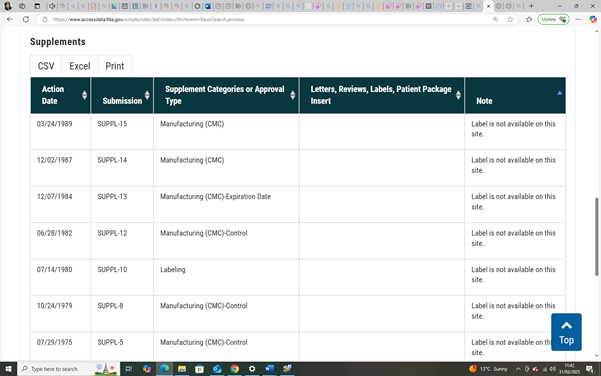

In 1949, the FDA had already approved a different drug: paramethadione, a structural analogue of trimethadione, both part of the oxazolidinedione class of anticonvulsants. Marketed under the name Paradione by Abbott Laboratories, paramethadione was prescribed in the U.S. for absence seizures (NCATS).

Paramethadione (marketed as Paradione by Abbott Laboratories) was distributed in the United States and Canada, where it was prescribed for absence seizures throughout the 1950s and 1960s (CMAJ, 1959; PDR, 1954). To date, aside from Canada, no verified evidence of its approval or distribution has been found in thalidomide-affected regions such as the UK, Australia, or Germany, supporting the theory that paramethadione did not appear in those markets.

Paramethadione: A teratogen quietly removed in Canada after its official last FDA order in 1989, making it impossible to attribute outcome shifts to known regulatory action (FDA, N.D). (See Report Section 12 – Foundational Studies).